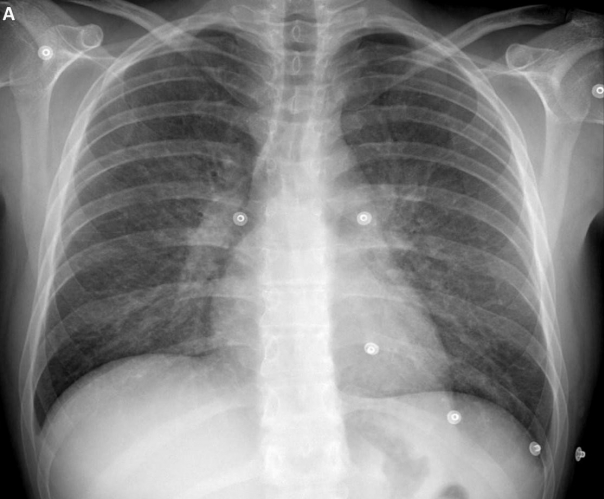

where is the pixel’s new gray level value, the values and are the pixels with the lowest and highest values low in the neighborhood and corresponds to the cumulative distribution function [38]. In Fig. 2 we present an example with the original and preprocessed image.

(A) | (B) |

---|---|

![]() |